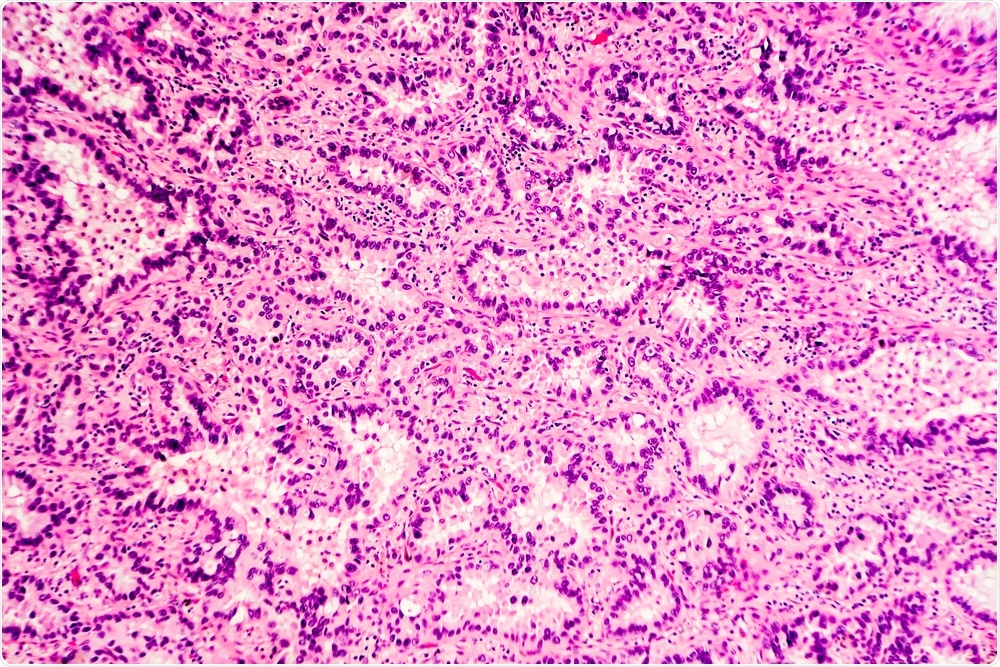

H&E stain of lung adenocarcinoma. (Image Credit: David A. Litman/Shutterstock.com)H&E stain of lung adenocarcinoma. (Image Credit: David A. Litman/Shutterstock.com)

Pathologists use many techniques to analyze a tissue. One of the most common is histological staining, which has been used as a diagnostic tool for over 100 years. Here, a section of tissue is stained with a non-specific dye and a pathologist examines the stained section of tissue under the microscope and makes diagnoses based on how cell morphology compares to a grading scale. In many cases, histology does not provide a clear diagnosis because of the subjective nature of the process.